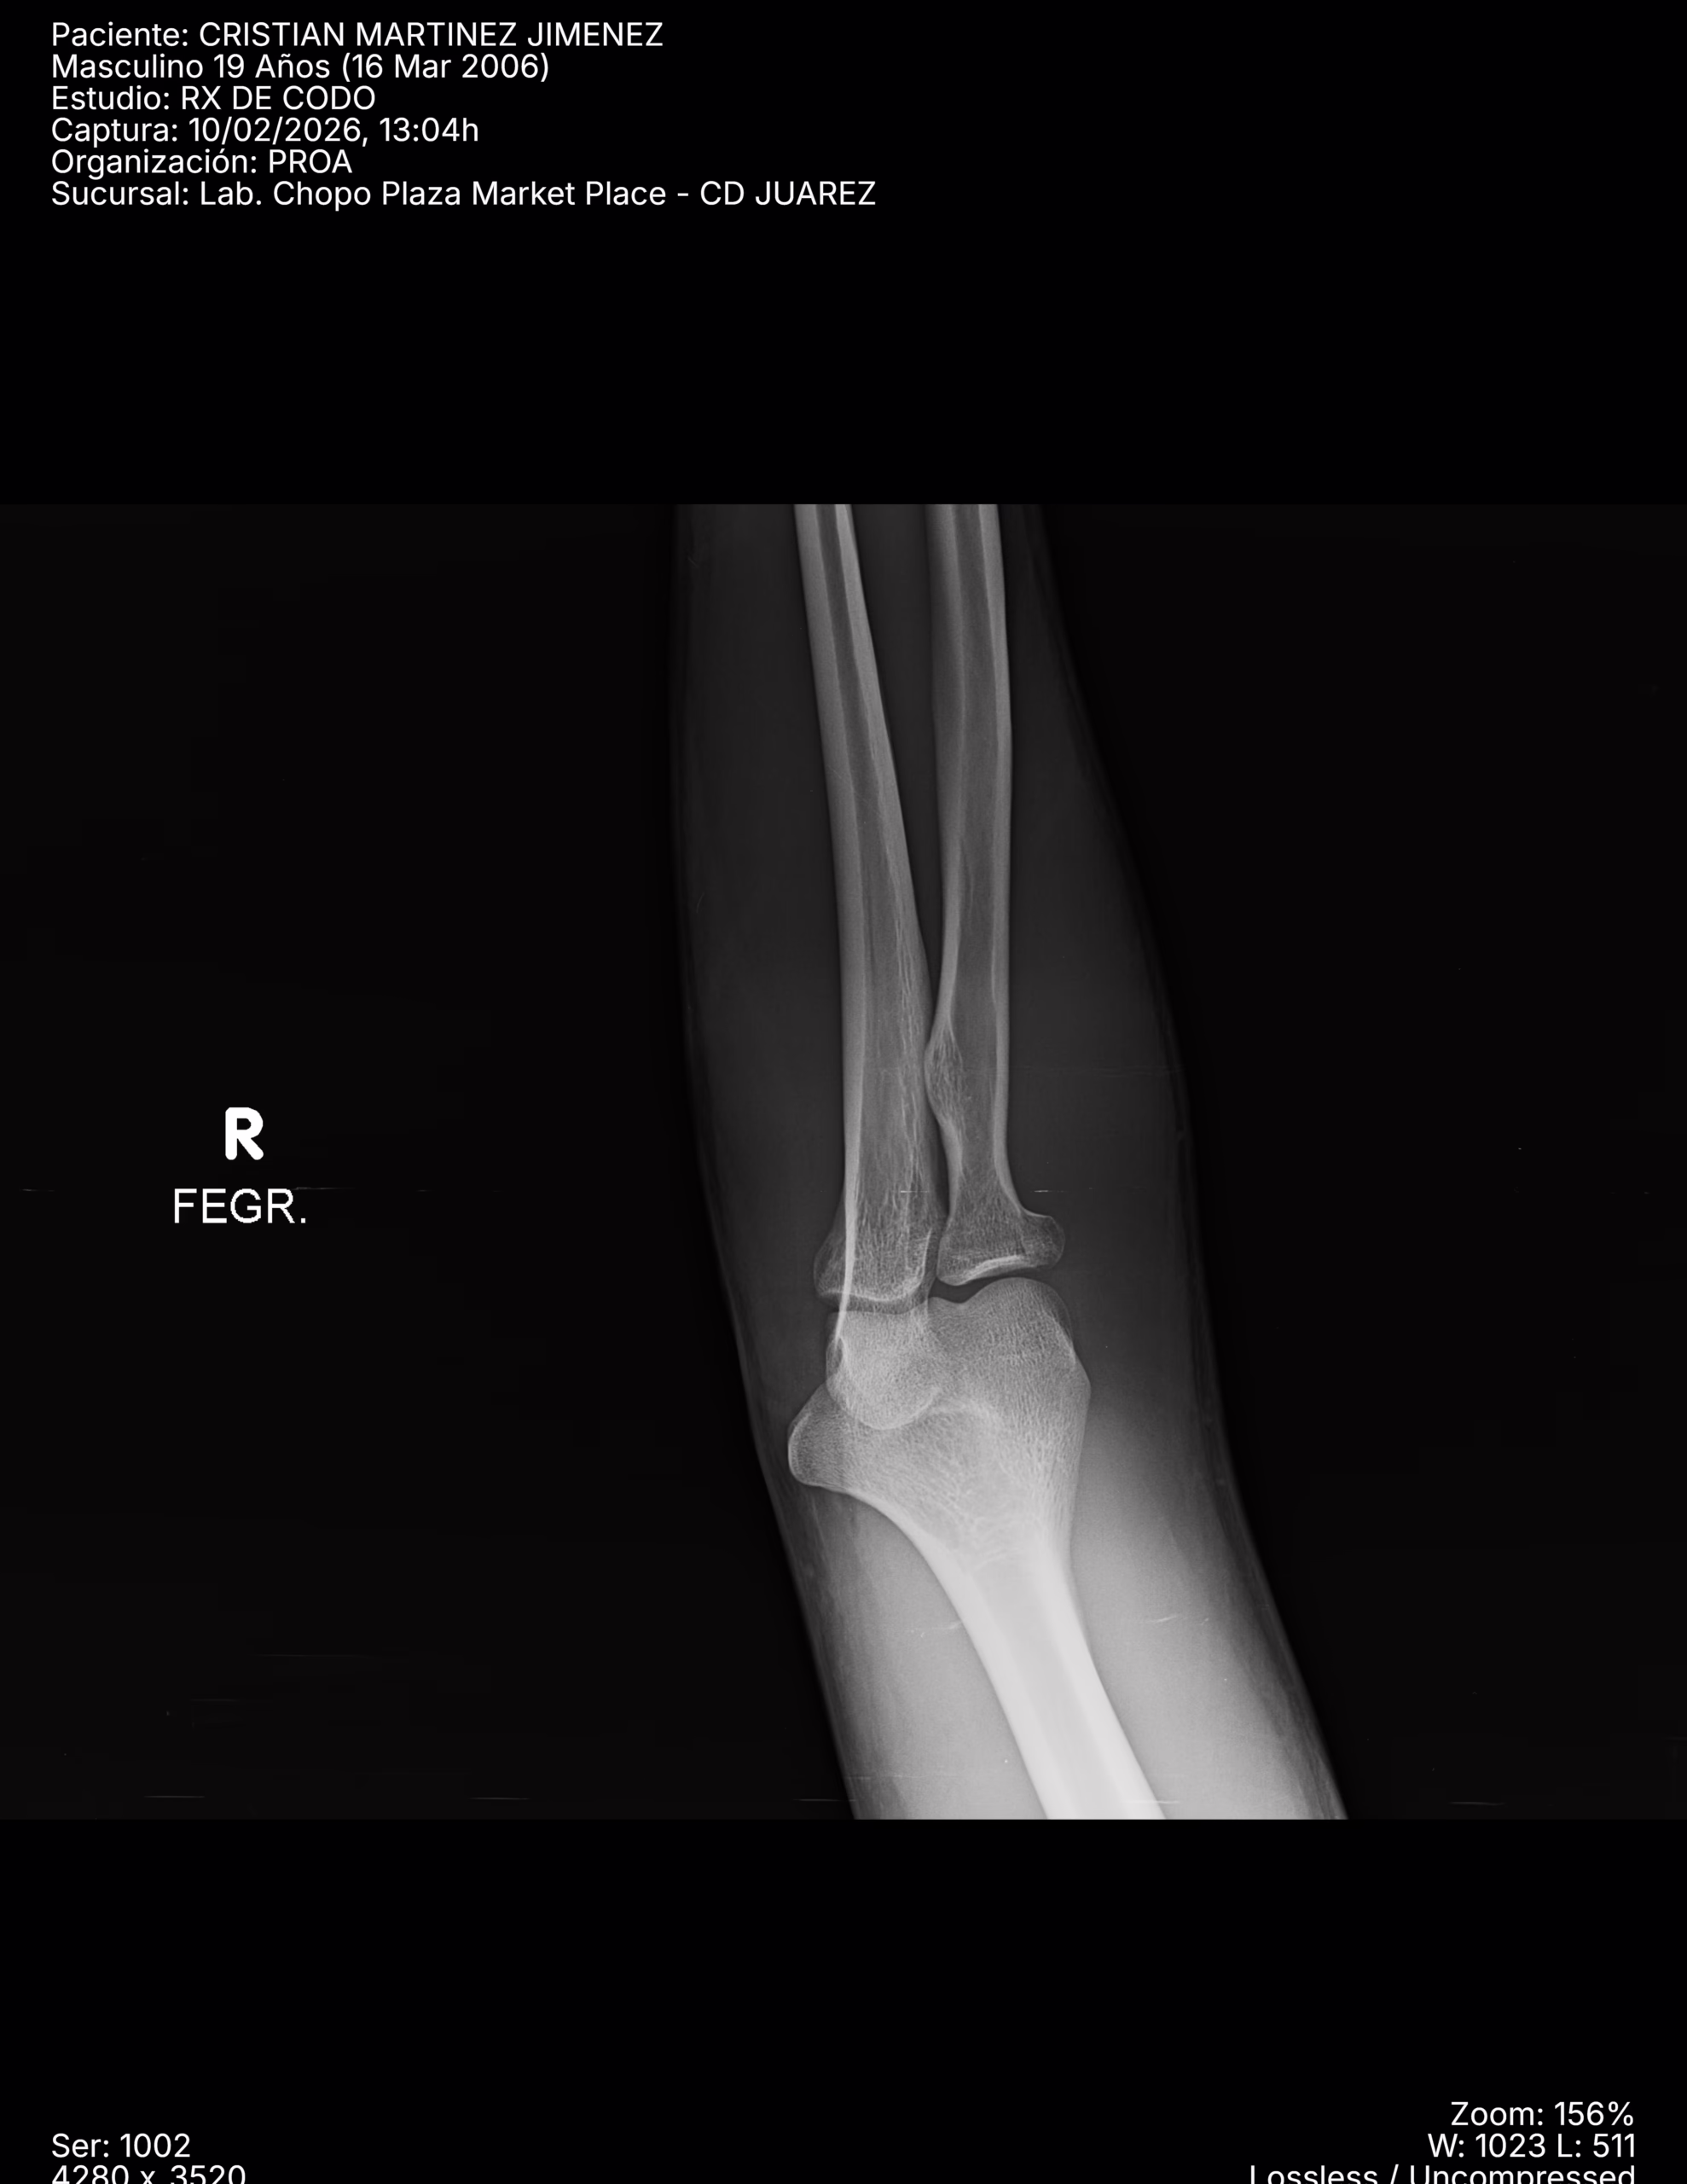

RADIOGRAFIAS AP Y LATERAL DE CODO

LAS PROYECCIONES RADIOLOGICAS OBTENIDAS NOS MUESTRA LOS SIGUIENTES HALLAZGOS:

-Tejidos blandos, a nivel de fosa de codo con aumento la densidad y grosor..

-Almohadilla grasa anterior, con el signo de la vela.

-Radio, con pérdida de la contigüidad a nivel de cabeza que involucra la porción medial, no desplazada. Resto de lo valorado de radio y cubito, sin evidencia de lesiones líticas, blásticas o perdida de la contigüidad.

-De lo valorado de humero, sin evidencia de lesiones líticas, blásticas o perdida de la contigüidad.

-Espacios articulares observados, sin evidencia alteraciones.

OPINIÓN RADIOLÓGICA:

− EN EL PRESENTE ESTUDIO RADIOGRÁFICO, EXISTE FRACTURA A NIVEL DE CABEZA DEL RADIO DE PREDOMINIO MEDIAL CON EDEMA ASOCIADO E INVOLUCRO ARTICULAR (HEMARTROSIS).

− LEER DESCRIPCIÓN Y OTORGAR VALOR DIAGNÓSTICO.

− CORRELACIONAR CON DATOS E HISTORIA CLINICA DEL PACIENTE.